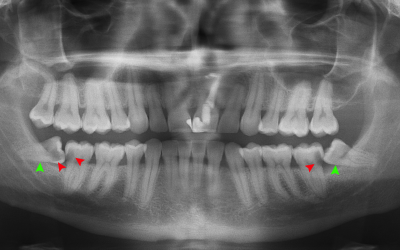

Panoramic X-Rays: A Comprehensive View of Your Oral Health

Panoramic X-rays offer a broad and detailed view of your oral health, providing crucial information for diagnosis and treatment planning. At Eastern...